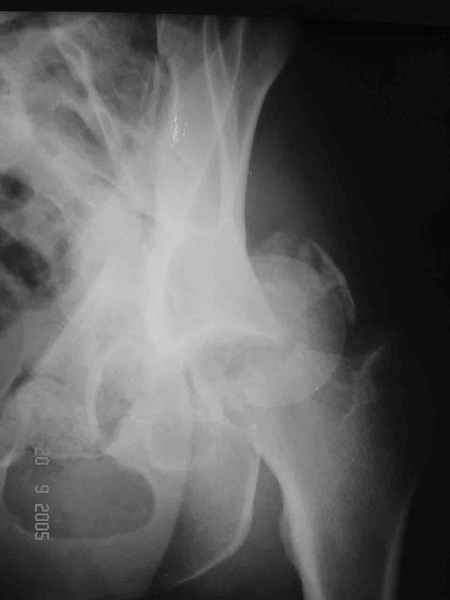

Больной 18 мая 2003 года в автоаварии получил перелом левой вертлужной впадины, вывих бедра. Госпитализирован в один из стационаров области.Вывих вправлен. В последствии бедро вывихивалось еще дважды. На консультацию был представлен снимок от 19.05.03г., больной переведен к нам 3.06.03г. Снимок при поступлении - перелом впадины, задне-верхний вывих бедра. 05.06.2003 г. выполнено открытое вправление вывиха левого бедра и остеосинтез стенки вертлужной впадины двумя винтами. Послеоперационный период без осложнений. Объем движений в левом тазобедренном суставе восстановился полностью. Выписан на амбулаторное лечение в удовлетворительном состоянии с рекомендациями 3 месяца ходить на костылях без нагрузки на оперированную конечность. На контрольных рентгенограммах левого тазобедренного сустава 13.10.2003 г. - признаки консолидации перелома; плотность, форма головки и состояние суставных поверхностей удовлетворительные. Разрешена дозированная осевая нагрузка, на конечность с использованием дополнительной опоры. 19.12.2003 г. больной обратился с жалобами на боли в левом тазобедренном суставе. На рентгенограммах левого тазобедренного сустава 19.12.2003 г., 20.02.04г. - асептичекий некроз головки бедра. 5.04.04г. - эндопротез. Сейчас ходит без трости, не хромает. Особенность эндопротезирования - при удалении винтов прослежена линия перелома заднего края впадины и предложено установить чашку несколько меньшего диаметра, чтобы она была покрыта несломанной частью.

Случай, представленный Вами, совсем не идентичен обсуждаемому. У Вашего пациента был поперечный перелом с переломом заднего края, а в обсуждаемом случае - высокий двухколонный перелом вертлужной впадины.

То есть в представленном Вами случае был перелом заднего типа, в нашем случае центрального. У Вашего больного был застарелый задний вывих, у нашего - перелом шейки. Столь раннее разрушение головки, вероятно, было во многом обусловлено тем, что не была достигнута анатомическая репозиция, головка бедра осталась смещенной кзади, что является частой ошибкой при крупных фрагментах свода.

Необходимость фиксации вертлужной впадины в нашем случае вообще под вопросом, так как конгруэнтность сохранена (вторичная конгруэнтность типична для двухколонных переломов).